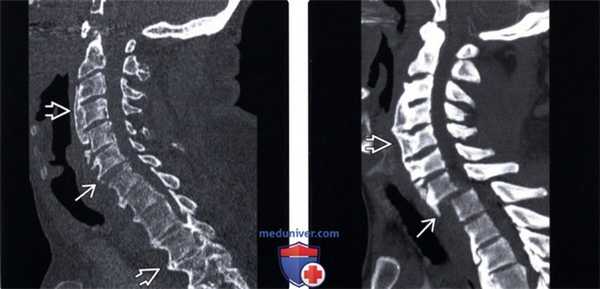

(Слева) Рентгенография в сагиттальной проекции: типичное наплывающее костеобразование, позволяющее диагностировать ДИСГ. Обратите внимание на то, что пространства дисков практически сохранены, однако на уровне С5-С6 визуализируется небольшое сужение. Значительных изменений в дугоотростчатых суставах не определяется. У пациента отмечается сильная боль в шее.

(Справа) МРТ, сагиттальная проекция, режим Т2 с подавлением сигнала от жира: у этого же пациента подтверждается наличие переднего костного образования, содержащего костный мозг. Тем не менее, дополнительно визуализируется грыжевое выпячивание диска на уровне CS-C6, которое является причиной боли в шейном отделе. Для ДИСГ не характерно наличие выраженного болевого синдрома, поэтому следует осуществить поиск других его причин. Патологические изменения диска и перелом с псевдоартрозом могут являться этиологическими факторами развития радикулопатии или миелопатии. Дисфагия является результатом формирования костного образования спереди. (Слева) МРТ, сагиттальная проекция, режим Т1. признаки ДИСГ. Исследование выполнено в правой парасагиттальной проекции. Передняя наплывающая оссификация выражена здесь в гораздо большей степени, нежели слева (не показано). Переднее костное образование берет начало непосредственно из центра тел нескольких позвонков и из нижнего и верхнею отделов тел других позвонков. И то и другое характерно для данною заболевания. Диски, а также дугоотростчатые суставы остаются неизмененными. ДИСГ не является истинной артропатией, однако в ряде случаев сочетается с дегенеративным поражением позвоночника.

(Справа) КТ, сагиттальная проекция: передняя наплывающая оссификация при ДИСГ. Соосность и дисковые пространства не изменены. Признаки остеоартроза апофизарных суставов не визуализируются. Обратите внимание на характерное, но не исключительное для ДИСГ костное образование, окружающее зубовидный отросток и переднюю дугу атланта.

(Слева) Рентгенография в боковой проекции, выполнена в отделении экстренной помощи после ДТП: массивный передний наплывающий остеофит, характерный для ДИСГ. Признаки отека превертебральных мягких тканей не визуализируются. Тем не менее, учитывая выраженность остеопороза и сращение шейных позвонков необходимо учитывать возможность перелома.

(Справа) КТ, сагиттальная проекция, костный режим: подтверждается перелом в виде морковного стержня на уровне С6-С7 В. Это было катастрофическое для пациента повреждение с массивным поражением спинного мозга в результате относительно легкой травмы. (Слева) Рентгенография в боковой проекции, после легкого ДТП: оссификация задней продольной связки, признак, который также встречается при ДИСГ. Передние остеофиты слились, сформировав сплошную колонну остеопорозной кости. Такой признак должен повышать вероятность наличия скрытого перелома в области шейно-грудною перехода, аналогично пациентам санкилозирующим спондилезом.

(Справа) КТ: подтверждается наличие перелома по типу морковного стержня со смещением. (Слева) КТ, сагиттальная проекция, без контрастною усиления: характерные для ДИСГ массивные передние остеофиты шейного и верхнегрудного отделов позвоночника.

(Справа) КТ, аксиальная проекция, без контрастного усиления: массивный остеофит у тою же пациента, смещающий левую сонную артерию и перекрывающий левый отдел гортанной части глотки. Крупные передние и переднебоковые остеофиты могут значительно затруднять глотание и иногда воздействовать на другие близлежащие структуры, как в этом случае.